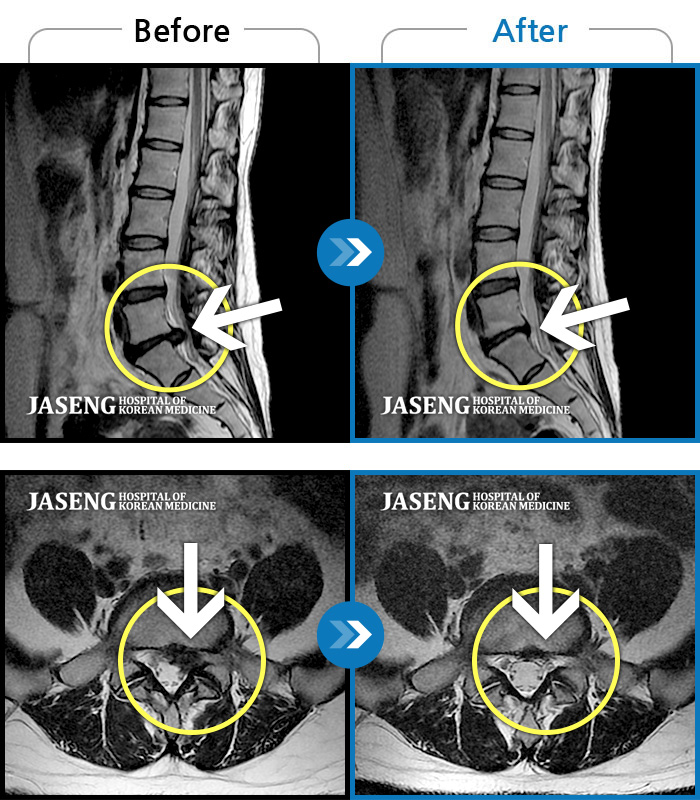

허리디스크

일산 · 김진수 원장

처음 내원 시 우측 엉덩이가 많이 아프고, 우측 다리로 근력 및 감각 저하도 있어 발목 움직임이 원활치 못했으며, 야간통으로 잠도 못 자고 통증 심하여 정상적인 활동이 힘든 상태셨습니다.

촬영시기

2023.12.04 ~ 2024.06.04

2024.06.21

조회수 564